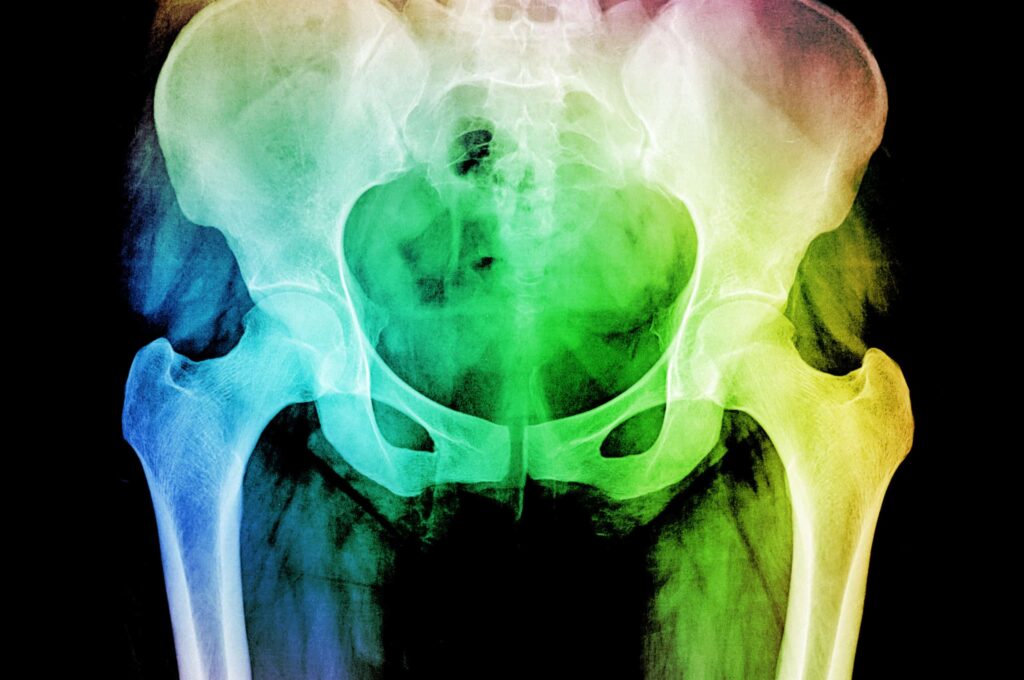

Radiotherapy is a highly effective treatment. As with all procedures, short-term side effects are common, however PRD covers a wide range of symptoms which start or continue at least three months after the end of pelvic radiotherapy. Without treatment these can be lifelong and can leave patients with permanent pain, bowel and bladder difficulties, bone fractures and nerve damage.

As the number surviving cancer grows, so do the number affected by PRD. The Pelvic Radiation Disease Association estimates that at least 100,000 people in the UK experience ongoing problems following radiotherapy to the pelvic region. 40% of cervical cancer patients receive radiotherapy as part of their treatment. Every year in the UK, over 3,200 women are diagnosed with cervical cancer with 49,000 living with or beyond diagnosis.